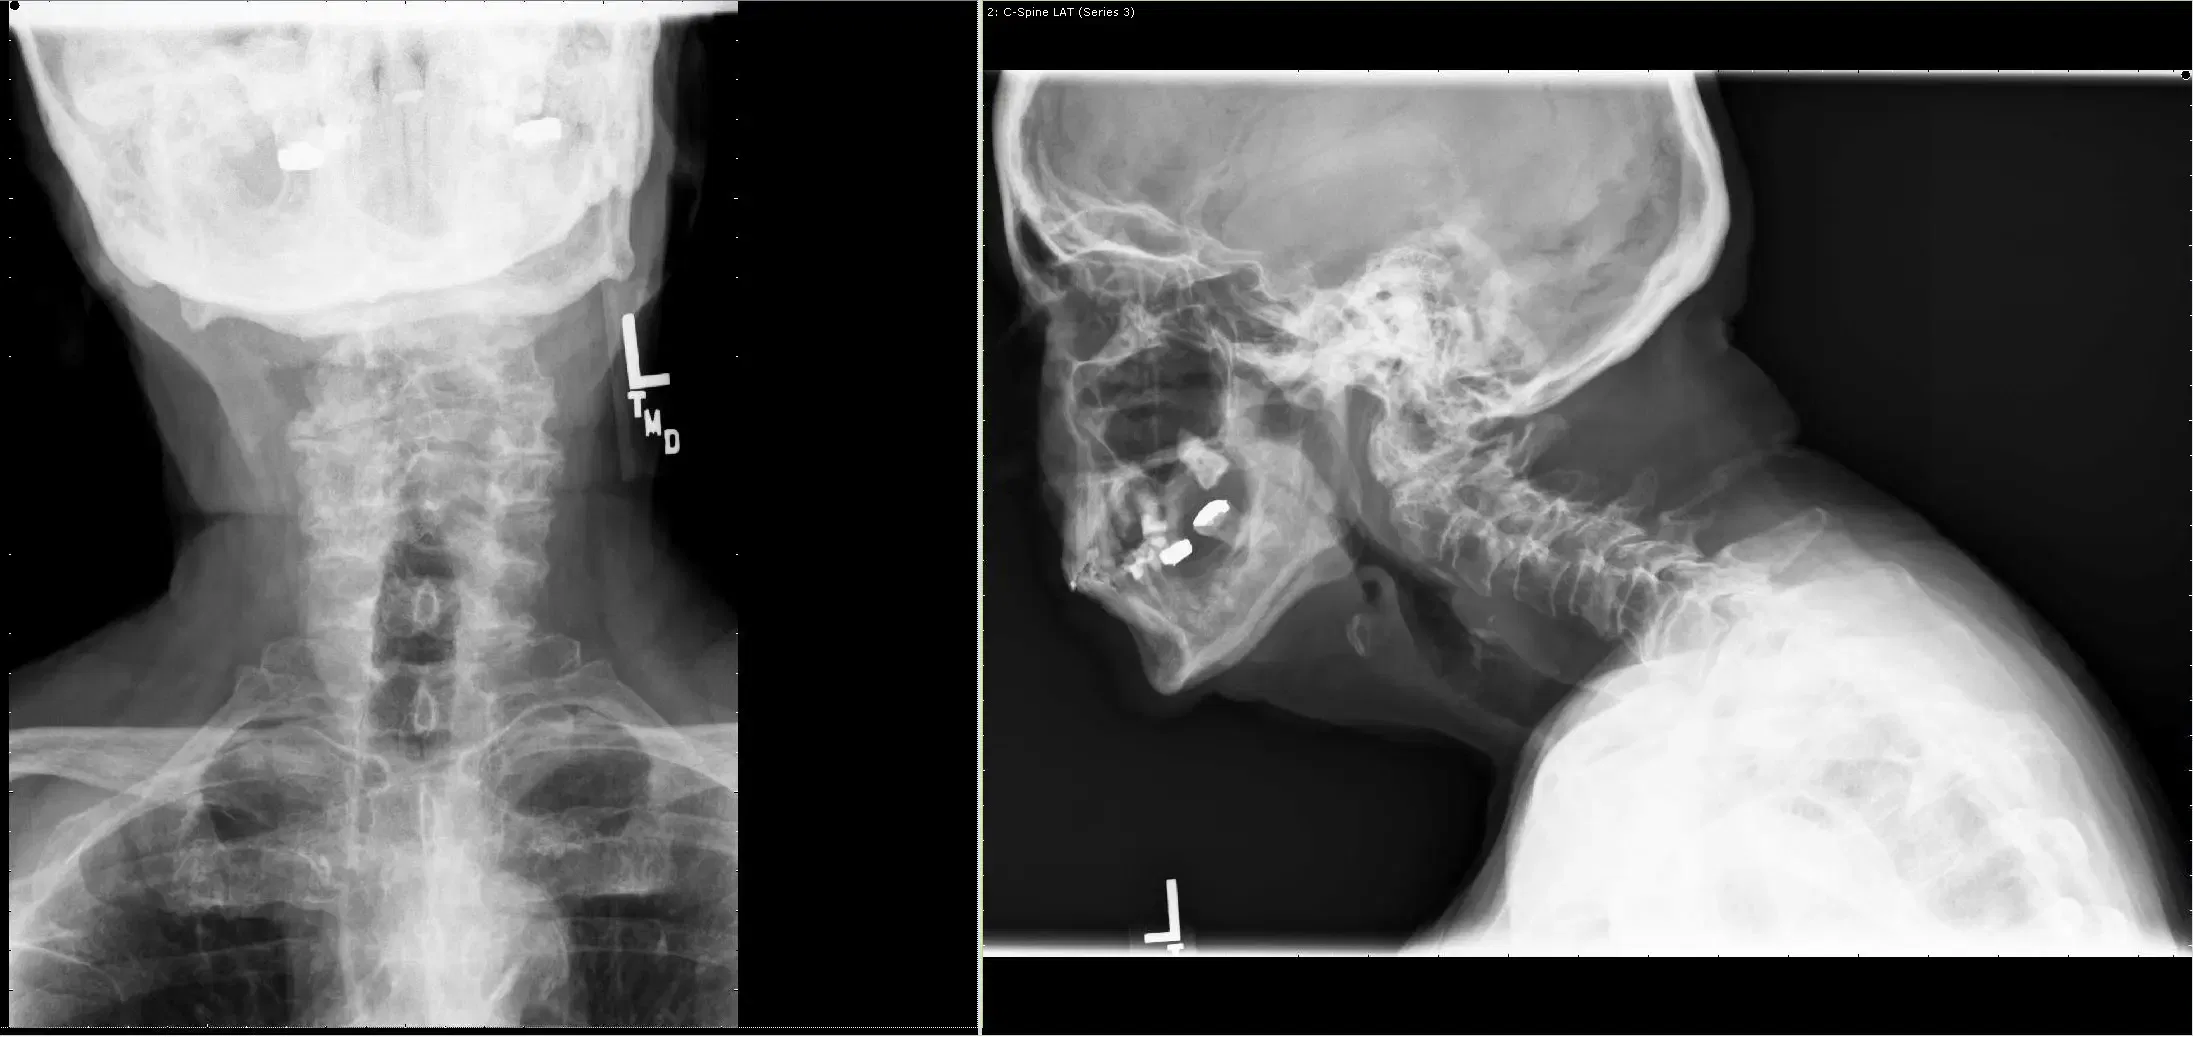

Tenía problemas de equilibrio junto con debilidad en las cuatro extremidades. Las radiografías, la tomografía computarizada y la resonancia magnética mostraron una no unión entre fractura odontoide y formación de panno y unión fibrosa, inestabilidad con compresión de la médula espinal a nivel C1-2.

Tras una discusión exhaustiva con el paciente, se planificó un manejo quirúrgico. Se realizó una descompresión posterior de C-12 con estabilización mediante fijación de tornillo y varilla C1-2.